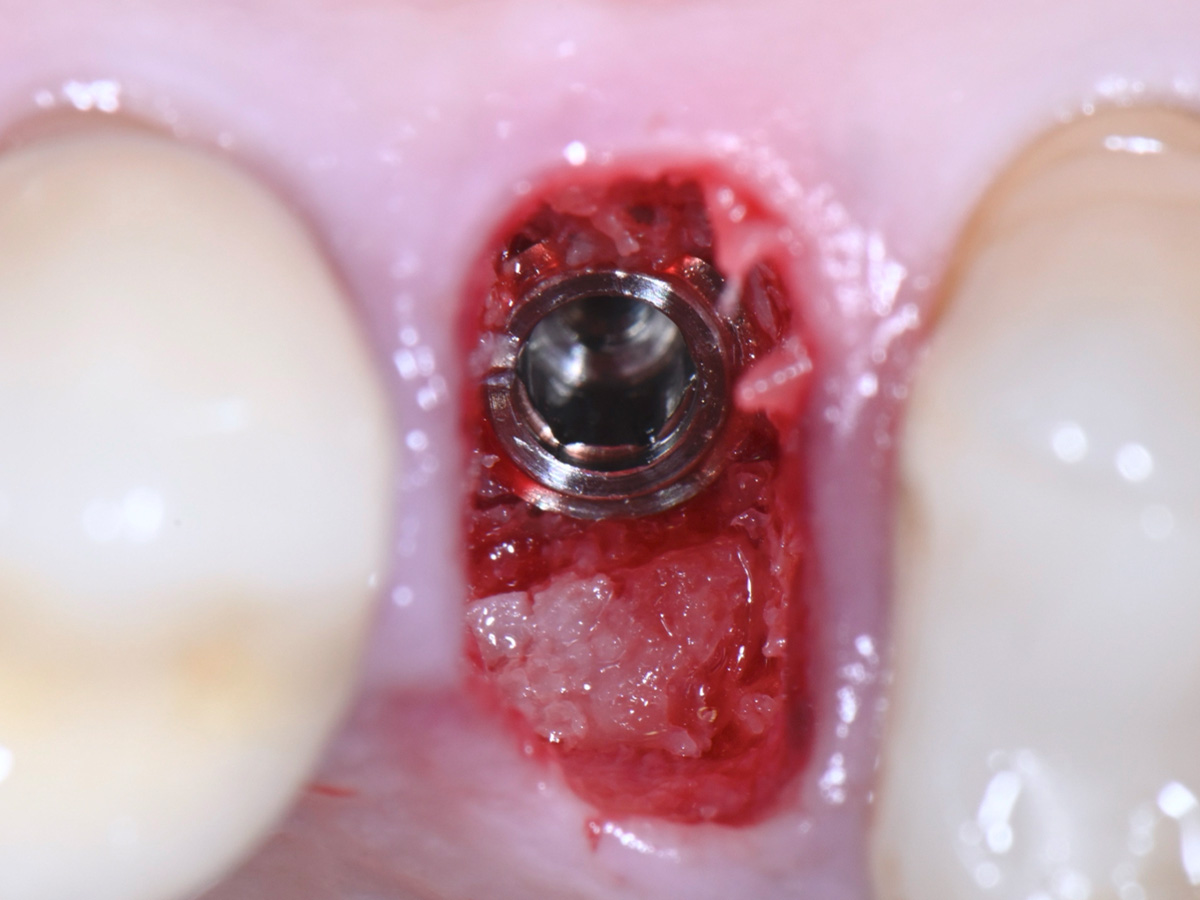

Abbildung 13

Defektrekonstruktion mit Hilfe des autologen Knochens unter Nutzung eines Gap-Pluggers

Abbildung 14

Mit Hilfe des autologen Knochens wird fast die gesamte Alveole rekonstruiert und ein Sofortimplantat darin stabilisiert